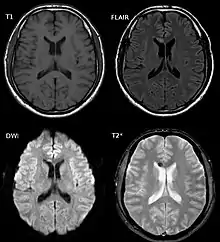

| Two MRI images of a patient with diffuse axonal injury resulting from trauma, at 1.5 tesla field strength. Left: conventional gradient recalled echo (GRE). Right: Susceptibility weighted image (SWI). | |

DAI is difficult to detect since it does not show up well on CT scans or with other macroscopic imaging techniques, though it shows up microscopically.[9] However, there are characteristics typical of DAI that may or may not show up on a CT scan. Diffuse injury has more microscopic injury than macroscopic injury and is difficult to detect with CT and MRI, but its presence can be inferred when small bleeds are visible in the corpus callosum or the cerebral cortex.[34] MRI is more useful than CT for detecting characteristics of diffuse axonal injury in the subacute and chronic time frames.[35] Newer studies such as Diffusion Tensor Imaging are able to demonstrate the degree of white matter fiber tract injury even when the standard MRI is negative. Since axonal damage in DAI is largely a result of secondary biochemical cascades, it has a delayed onset, so a person with DAI who initially appears well may deteriorate later. Thus injury is frequently more severe than is realized, and medical professionals should suspect DAI in any patients whose CT scans appear normal but who have symptoms like unconsciousness.[9]

MRI is more sensitive than CT scans, but is still liable to false negatives because DAI is identified by looking for signs of edema, which may not always be present.[33]